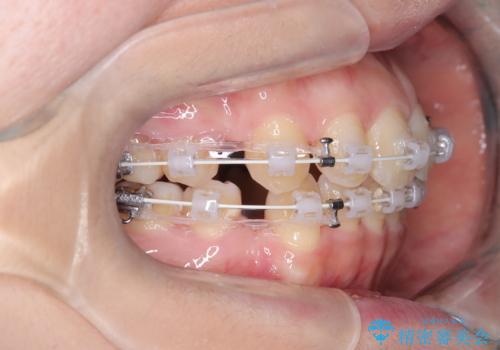

- 矯正装置

- ワイヤー(審美装置)

- 「歯のデコボコと前歯が出ているせいで口が閉じにくい」を主訴に来院された患者様です。

上下左右の4番(第一小臼歯)を抜歯をし審美ワイヤー装置で治療を行いました。